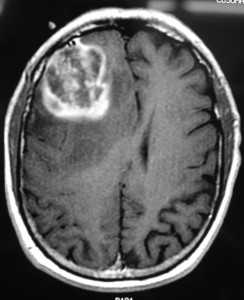

Глиобластома: симптомы, выявляемые с помощью МРТ. Аксиальный срез в режиме Т1 после контрастирования препаратом гадолиния демонстрирует распространенную опухоль правой лобной доли. Изображение предоставлено доктором George Jallo.

Как выглядит глиобластома на МРТ? Как правило, образование на томограммах представляет собой зону, имеющую в основном пониженный сигнал на Т1-взвешенных изображниях и повышенный сигнал на Т2- взвешенных изображениях. Могут присутствовать внутренние кистозные участки, участки потери сигнала, обусловленные крупными сосудами, внутренние зоны повышенной интенсивности сигнала на Т1-ВИ (геморрагические очаги), новообразованные сосуды, очаги некроза, обширный перитуморозный вазогенный отеком и значительный масс-эффект. Также может выявляться неравномерное, но интенсивное накопление контрастного вещества на основе гадолиния (та же картина наблюдается на КТ после введения йодсодержащего контраста), как в основной опухоли, так и в метастатических очагах, характерных для МФГ. МРТ более чувствительна к этим изменениям, чем КТ.